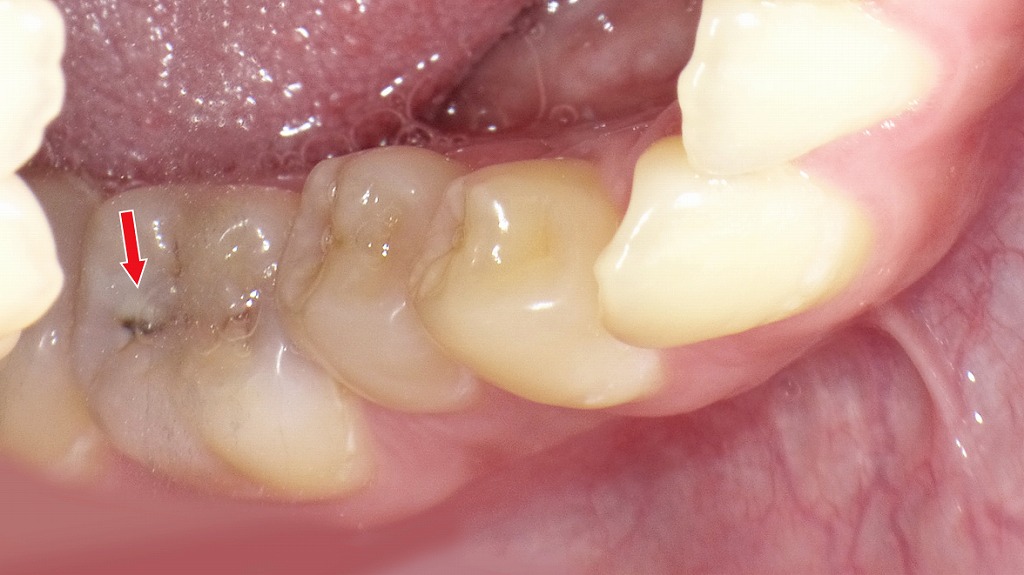

歯と歯の間の黒い点は要注意|レントゲンで発見できる“隠れ虫歯”

赤矢印が示すように、歯と歯の間(コンタクト部)の初期虫歯は、肉眼ではほとんど確認できません。レントゲンを撮影することで、エナメル質内部の透過像として虫歯を早期に発見できます。見た目に穴がなくても進行している場合があるため、定期的なレントゲン検査は非常に有効です。